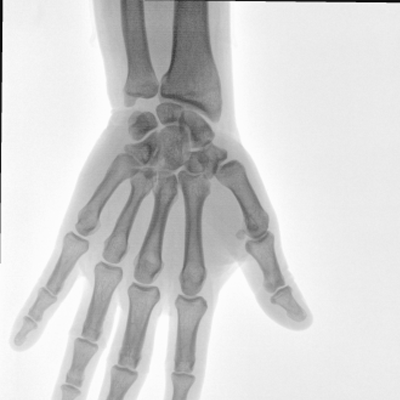

大尺寸動態(tài)平板探測器,高DQE、低噪聲、圖像清晰。采用多分辨率圖像增強處理技術(shù),不同部位不同圖像處理算法,滿足客戶多樣化的需求。

采用智能變頻脈沖透視技術(shù),優(yōu)化圖像質(zhì)量的同時降低輻射劑量,呵護醫(yī)患健康